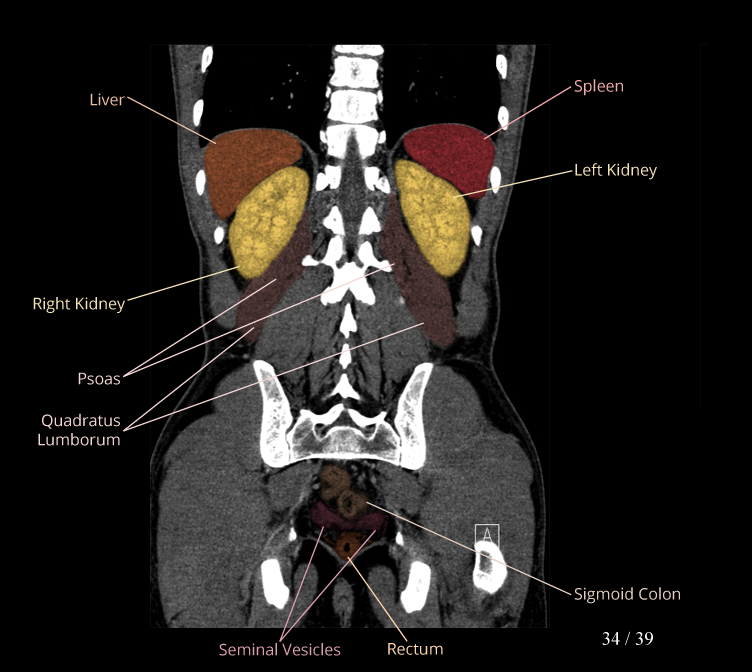

Body

Covers abdominal CT anatomy.